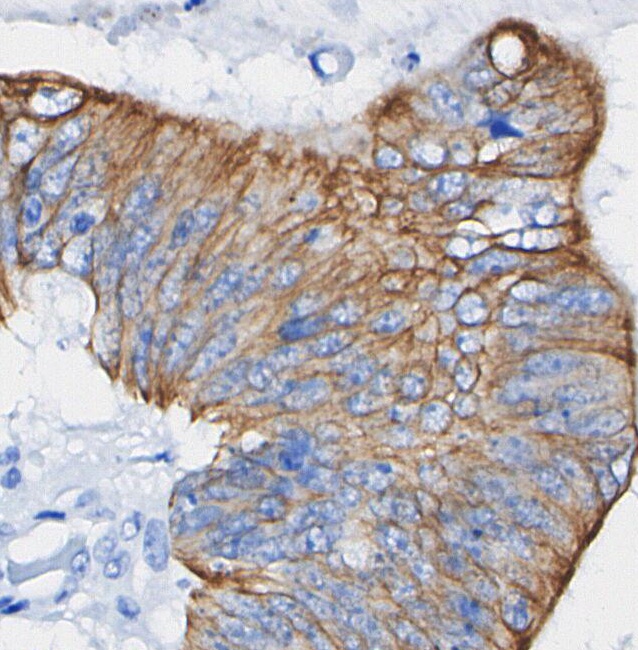

• Immunohistochemical analysis of formalin fixed paraffin embedded human Colorectal cancer tissue with F1042 at 1/100 dilution.